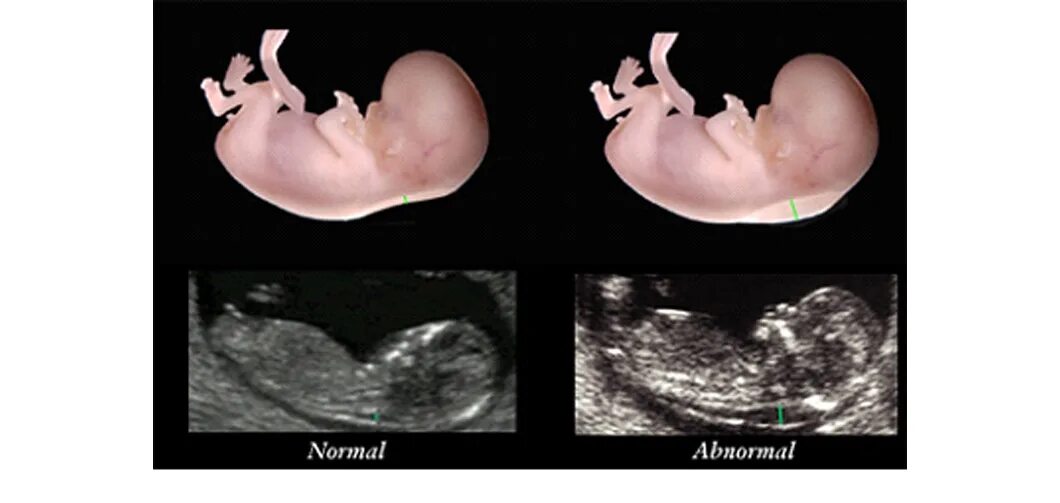

Воротниковая пространство форум